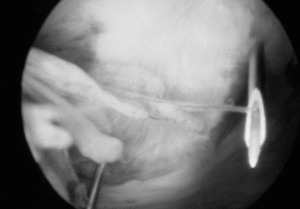

La acromioplastia por vía artroscópica fue descrita por Ellman16 para los estadios II y III de Neer (fig. 3), dando a conocer los resultados preliminares de las primeras descompresiones subacromiales por artroscopia, en las que se reseca la superficie anteroexterna del acromion, se efectúa una bursectomía en los pacientes más jóvenes, y se desinserta el ligamento coracoacromial.

Figura 3. Delimitación del ligamento coracoacromial con dos agujas según la técnica de Ellman.